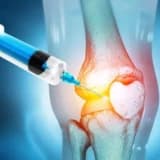

Kök hüceyrələr oynaq və qığırdaq zədələnmiş bir çox xəstəyə tətbiq oluna bilər. Ancaq bəzi xüsusi hallarda, kök hüceyrə tətbiqindən uzaq qaçmaq faydalıdır.